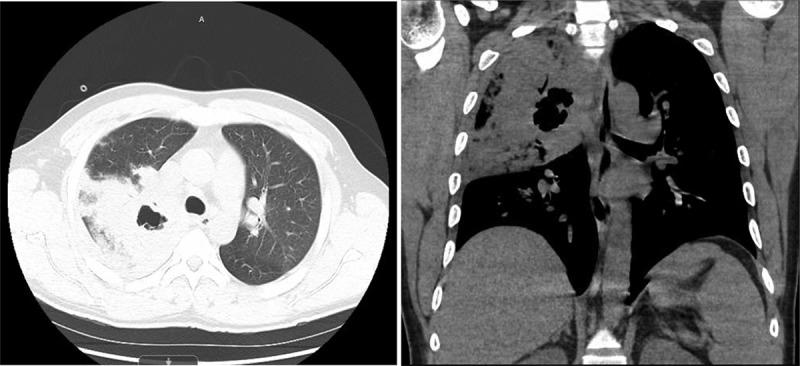

Hemorrhagic pneumonia and upper lobe pulmonary cavitary lesion caused by .

A 33-year-old previously healthy man from Mexico who presented with massive hemoptysis, fevers, chills and found to have cavitary lesions in the right upper lobe of lung was highly suspicious for tuberculosis. The patient was treated with vancomycin, ceftriaxone, azithromycin and placed on isolation for suspected tuberculosis. Sputum AFB stains were negative and blood cultures grew Group A Streptococcus [GAS]. Antibiotics were narrowed down to ampicillin-sulbactam and the patient was discharged with significant clinical improvement. Strep A pyogenes is a rare cause of cavitary hemorrhagic pneumonia but is associated with high mortality. Clinical suspicion and early diagnosis are crucial in saving the patient.